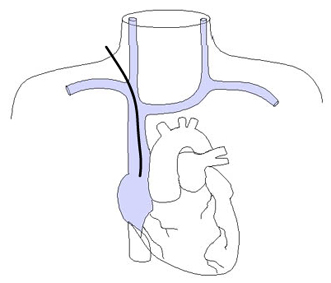

-Der Verlauf zum Herzen soll geradlinig sein, um Wandkontakt des Katheters mit Intimaläsionen und nachfolgender Thrombose zu vermeiden.

Diese Anforderungen treffen ausschließlich auf die proximale rechte Vena jugularis / Vena anonyma zu, die deshalb als Standardzugang verwendet werden sollte, zumal diese Punktion auch besonders einfach unter sonographischer Kontrolle erfolgen kann.

Die Vena jugularis/ Vena anonyma kann nach Yoffa zwischen medialem und lateralem Kopf des Musculus sternocleidomastoideus von ventral punktiert werden oder horizontal von lateral. Diese Methode wurde 1972 von den amerikanischen Herzchirurgen Garcia, Mispireta und Pinho nach ausführlichen anatomischen Präparationen als einfachster und ungefährlichster Zugang beschrieben. Das Zielgebiet, der Zusammenfluß von Vena jugularis und Vena subclavia zur Vena anonyma ist so groß, dass die Punktion auch ohne Sonographie immer beim ersten Stich gelingt.

Argumente gegen Punktion von links

Von links eingeführte Katheter stoßen in der in mehreren Ebenen gewundenen Vena brachiocephalica an die Venenwand an und verursachen Intimaläsionen und Thrombosen. Die Wandschäden sind umso schlimmer, je steifer der Katheter ist. Die schlimmsten Schäden rufen die in der Intensivmedizin üblichen lage bore Katheter hervor.

Etwa 10% der Bevölkerung haben als embryologisch bedingte Anomalie eine links persistierende obere Hohlvene, die meist in den Sinus coronarius mündet. Liegt ein von links eingebrachter Katheter im Sinus coronarius, dem venösen Abfluß des Herzens, kann die Infusion hochosmolarer Ernährungslösungen oder irritierender Zytostatika zu einer akuten Sinusthrombose mit Behinderung des venösen Abflusses aus dem Myokard führen. Der Anstieg des myokardialen Perfusionsdruckes führt zu einer Ischämie auch bei gesunden Koronararterien mit Infarkten, Arrhythmien und plötzlichem Herztod (W Masood, KK Sitammagari: Coronary Sinus Thrombosis. StatPearls Publishing; 2020 ).